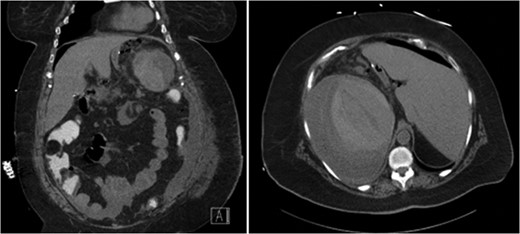

She represented 8 days after discharge with complaints of left upper quadrant abdominal pain. She denied dizziness, shortness of breath, chest pain or trauma to her abdomen. On physical exam her heart rate (HR) was unchanged from discharge at 104 bpm; however, she was noted to be hypotensive with a blood pressure (BP) of 86/44 mmHg and oxygen saturation 98% on 3 l. She received multiple fluid boluses in the emergency department and while her HR remained elevated at 104 bpm, her BP increased to 124/79 mmHg. A computed tomography (CT) scan with oral and intravenous contrast was obtained and demonstrated a large mixed attenuation fluid collection with scattered pockets of air within the splenic capsule without evidence of free intra-peritoneal air (Fig. 1). Upon laboratory analysis she was without a leukocytosis and her hemoglobin was decreased; however, unchanged from her previous discharge. It slowly declined throughout her readmission. On post-operative Day 12 her hemoglobin (Hgb) was 7.8, and she received two units of packed red blood cells with an appropriate increase in her Hgb. After initial transfusion of two units of packed red blood cells her hemoglobin and vital signs remained stable.

CT abdomen demonstrating air and fluid contained with the splenic capsule.